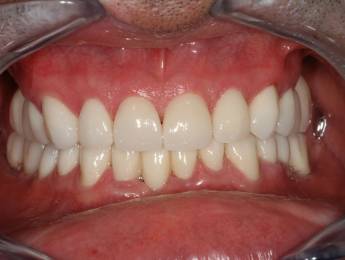

6. Eset

Nagymértékű fogkopás, erózió, csikorgatás a teljes rágóapparátust túlterhelve okoz reménytelennek tűnő helyzeteket.

Ebben az esetben implantátumok , koronák és hidak segítségével változtattunk a páciens fogainak érintkezésén. 6 hónapig ideiglenes hidakkal teszteltük a megváltoztatott harapási pozíciót. Ezután készültek el a végleges fix pótlások.